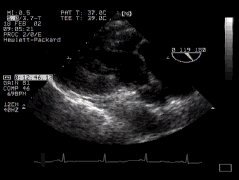

1. Two chamber view (LA, LV, MV) - 'TG 2 Chamber'

2. The anterior mitral leaflet (aml) is well seen, as well as the left ventricular and atrial chambers. The inferobasal portion of the left ventricle is particularly well seen in this view - perhaps the major justification for this particular part of the TOE examination! (The inferobasal part is that part of the LV in the upper portion of the image, close to the probe). Remember that in the visible human from which these anatomical sections were taken, the left side is particularly poorly filled, and thus the LV cavity appears much plumper in the echo image. Compare the above with the two-chamber mid-oesophageal view.